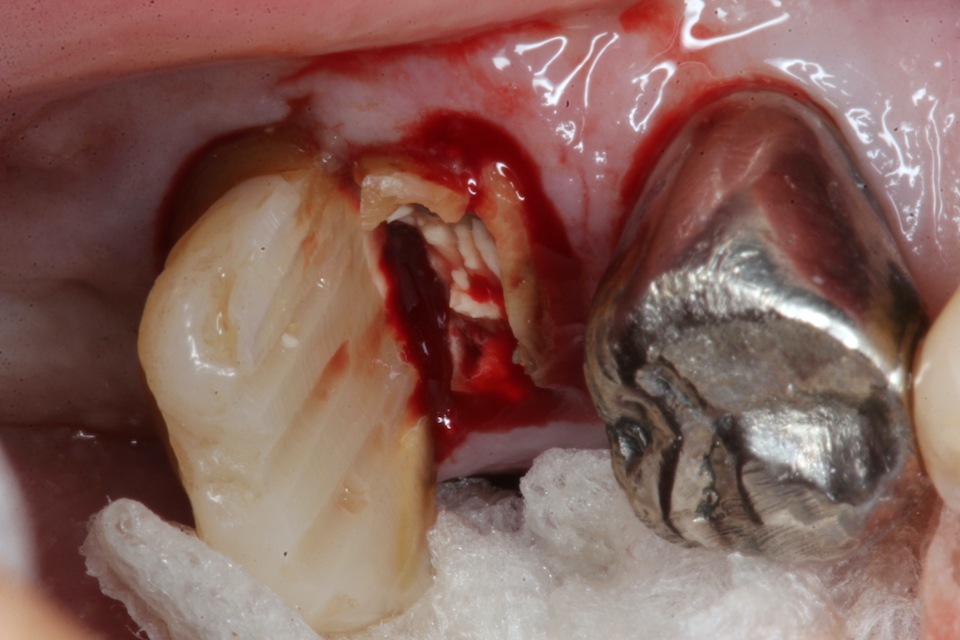

今日の抜歯再植術シリーズ39.1 2025.11.14

今日の抜歯再植術シリーズ39.0 2025.11.13

今日の抜歯再植術シリーズ38.3 2025.10.14